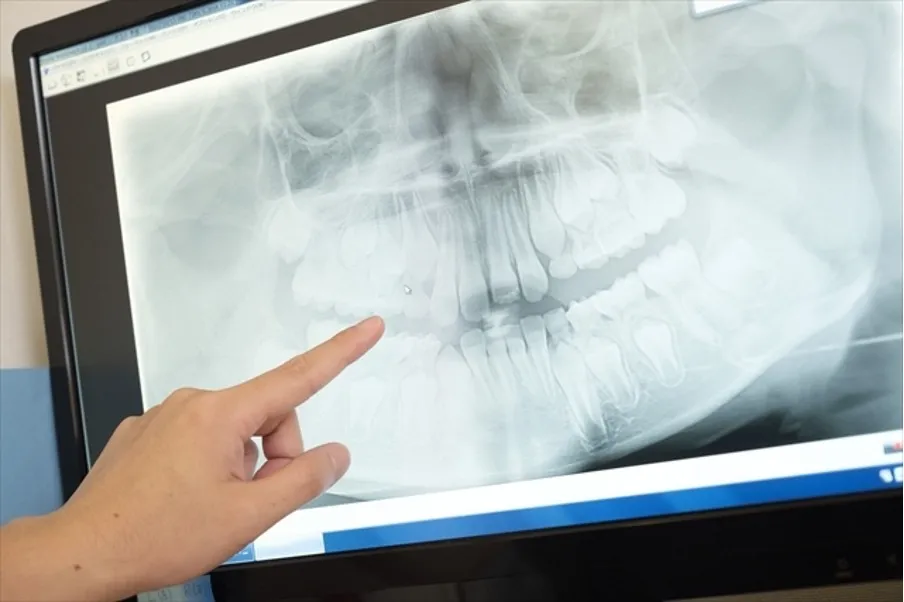

• STEP4 診査・診断

レントゲン撮影、歯周病検査、CT撮影などを実施します。

口腔腫瘍は、腫れや痛みを伴う舌や歯ぐきにできる腫瘍ですと比較的気づきやすいのですが、顎の骨の内部にできるような腫瘍は気づきにくく、自覚症状がないまま進行してしまうこともあります。定期的な検診やレントゲン撮影ではじめて見つかることも多いです。